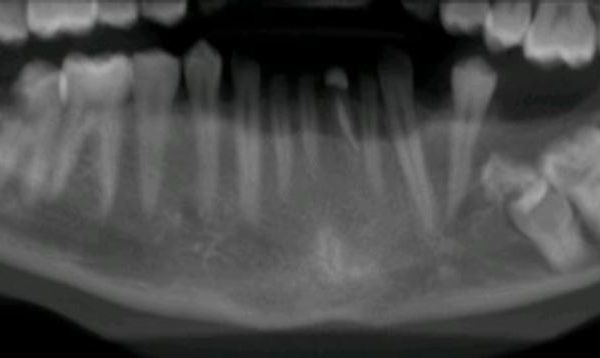

Case of the month – planning for dental implants

CT Dent’s latest case of the month on planning for dental implants includes; the main findings, findings from the radiographic…

Implant dentistry

Case of the month – pre-implant assessment

Basic report for pathology only CBCT scanner: Kavo OP 3D Vision V17 CBCT imaging protocol: 16cm diameter x 10cm height Effective dose: 0.1…

Dentistry